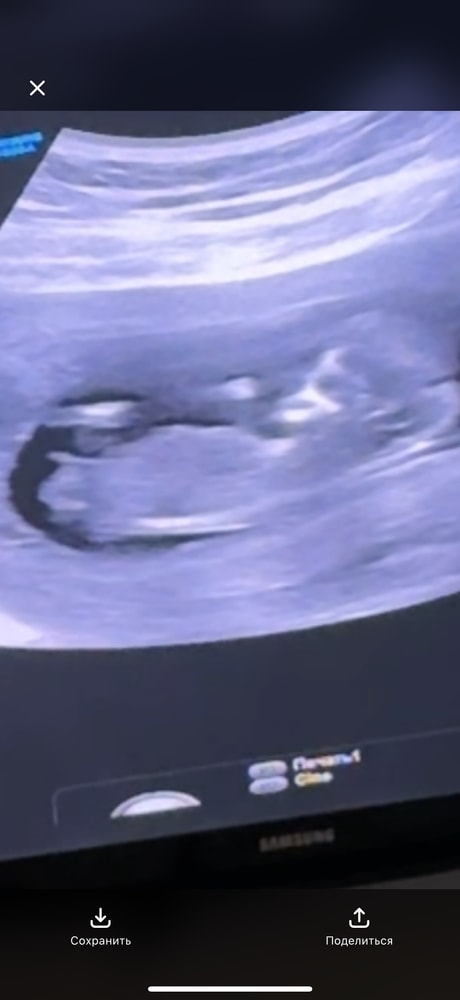

Кто определит пол 12 недель ?

Нормальный у вас подьем 😅 мальчик же

Мальчик🙂

Я за мальчика

Я больше склоняюсь к девочке 👧

Половой бугорок горизонтально у девочек)где тут кто какой то подьем увидел не пойму) На первом скрининге у меня так же было,ждем девочку

Я бы тоже сказала, что мальчик.

Девочка

Мальчик